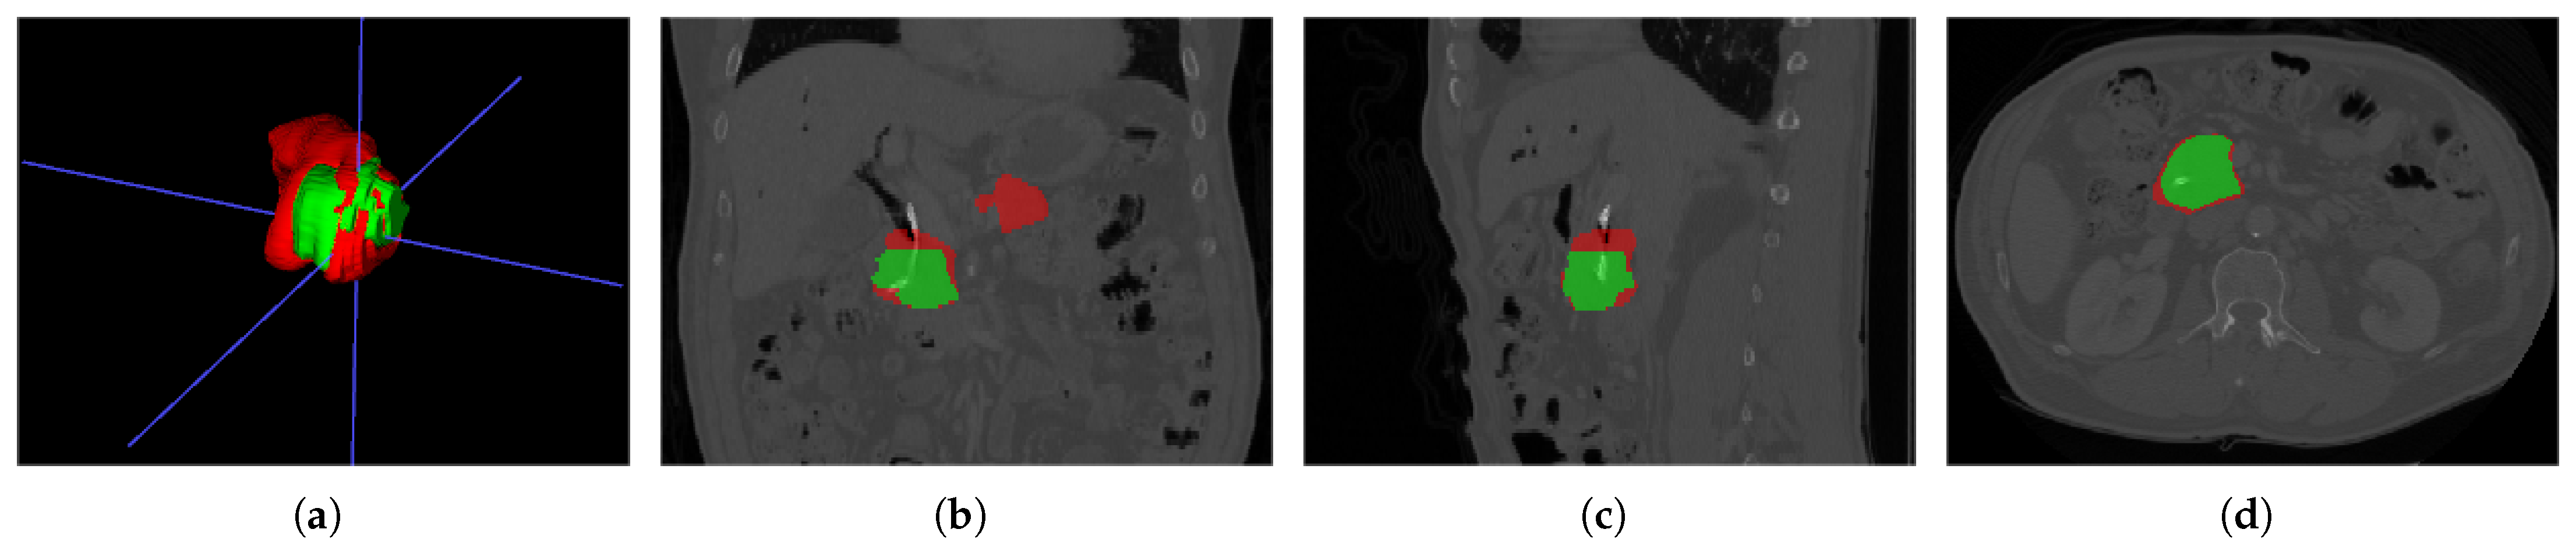

The dataset is based on EUS and consists of 420 patients and 3500 images. Its task is to classify PCs and non-PCs. Experienced physicians annotated these 3500 images with category labels. In addition, there are 8000 unlabeled images for pretraining. Sample images from LEPset are shown in Figure 4, with images labeled as PC or non-PC and unlabeled data.

Figure 4.

LEPset sample data: (a) labeled non-PC, (b) labeled PC, and (c) unlabeled image.